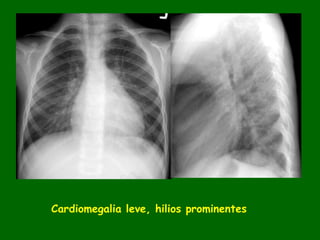

Cardiomegalia leve, hilios prominentes

Hallazgos radiológicos. • Dependiendodel tamaño del defecto. • Hilios prominentes. • Incremento de la vascularidad pulmonar. • Silueta cardiaca normal o ligeramente incrementada y pude ser prominente la aurícula derecha. • El crecimiento del VD en los adultos se aprecia por la disminución del espacio retroesternal.